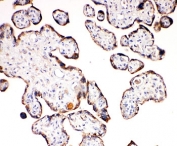

IHC-P: Aquaporin 6 antibody testing of human placenta tissue